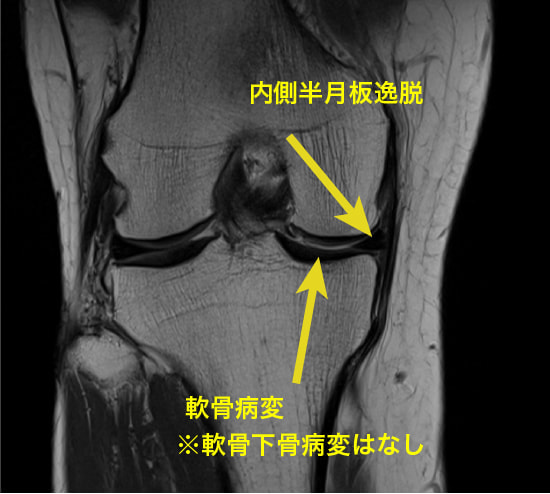

症例:半月板の逸脱

半月板hoop機能(荷重ストレスの分散)の破綻が急激な変形性膝関節症の進行の一因とされています。

軸方向の機械的ストレスの約70%が半月板を介して分散されていることを考えれば、半月板の損傷や逸脱によって変形性膝関節症に発展することは想像ができるでしょう。

内側半月板の前角と後角は、関節包や靭帯と連続しつつ、骨へ強固に付着しています。この骨への付着部は、半月板が関節にかかる荷重を分散する際の固定点として機能し、適切な位置で半月板が荷重を受けることを可能にします。特に、内側半月板の後根部の付着は、関節の荷重負荷に対抗するための重要な要素です。

半膜様筋が関節包に付着し、その関節包の張力に関与しているため、内側半月板の逸脱に関してのターゲットは「膝関節のアライメント調整」と「半膜様筋の促通」です。